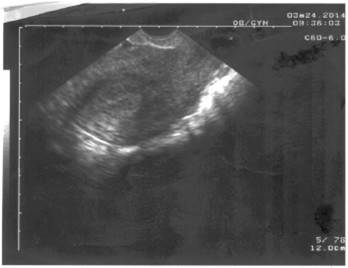

Se realizó ultrasonido ginecológico transvaginal, que reveló el útero de tamaño normal, sin dispositivo intrauterino y sin alteraciones anexiales. (Figura 3).